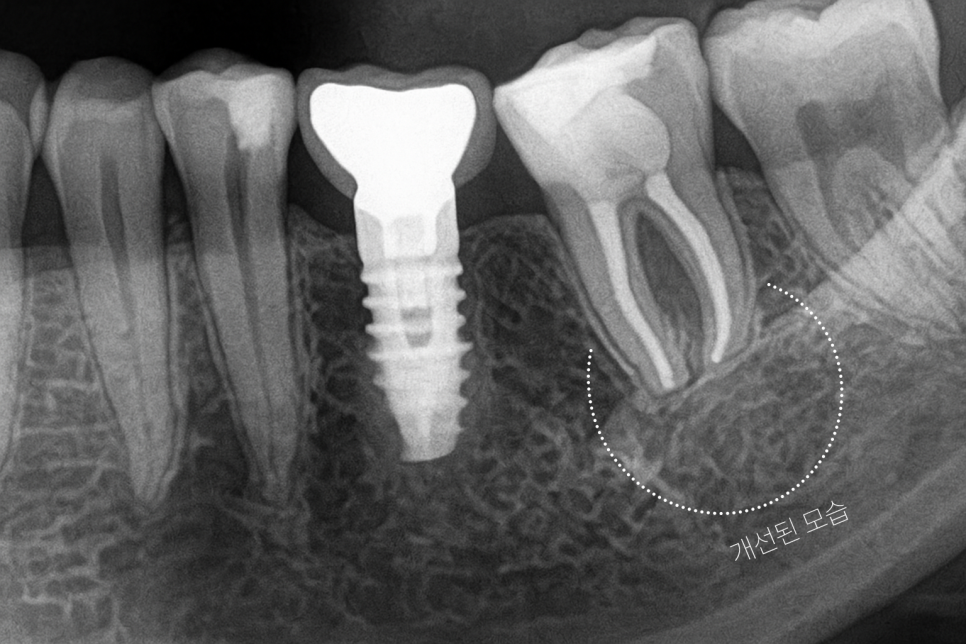

5️⃣ 이렇게 모든 절차가 마무리된 후

2~3개월가량은 꾸준히 경과를

지켜보며 예후를 살핍니다.

위 사례의 경우 다행히 잘 이루어져

염증 문제가 많이 개선되는

차도를 보였습니다.